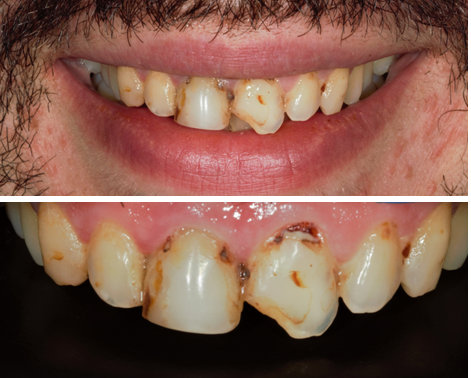

Εικόνα.

Ο ασθενής έχει εκτεταμένες αποκαταστάσεις παλιών δυσχρωμικών συνθέτων ρητινών με επανατερηδονισμούς στα όρια. Επιθυμεί βελτίωση της αισθητικής των μπροστινών δοντιών με την ελάχιστη παρέμβαση.